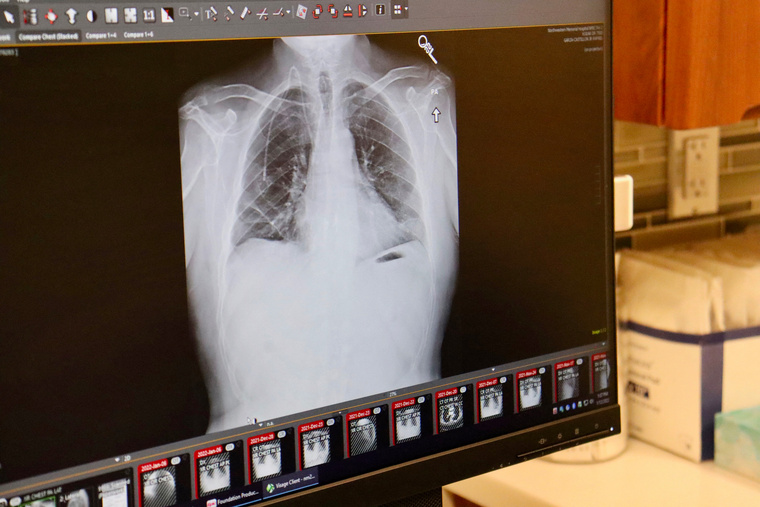

Ils seront appelés à faire deux scanners thoraciques à faible dose à un an d'intervalle, puis tous les deux ans, et se verront également proposer un sevrage tabagique.

Puis plusieurs études ont démontré les bénéfices d'un dépistage organisé du cancer du poumon: un scanner à basse dose chez des personnes à risque permet de détecter tôt des petites tumeurs débutantes et de réduire d'environ 20 à 25% le risque de décès.

L'objectif est de déterminer les modalités les plus efficaces et les plus sûres d'un dépistage par scanner thoracique: durée, fréquence, rôle de l'intelligence artificielle, impact économique, retentissement sur l'offre de soins, etc, selon le président de l'Inca.